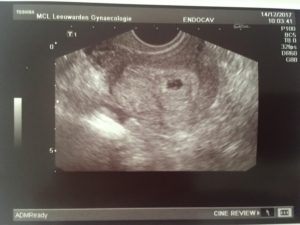

В этот же период начинается рост плаценты – уникального органа, обеспечивающего защиту и питание плода. Из трофобласта и эктодермы образуются амнион и хорион. Амниотическая полость заполняется околоплодными водами, а хорион начинает активно продуцировать ХГЧ. Размеры эмбриона достигают значения в 4 мм и его уже можно увидеть на УЗИ.

После проведения анализа на содержание в крови хорионического гонадотропина женщина уже может знать, что она носит в себе новую жизнь. Спустя 3 недели беременности, что происходит с плодом – можно разглядеть с помощью ультразвукового исследования.

На этом этапе эмбрион представляет собой крошечный шар с едва различимыми головным и хвостовым концами, окруженный плодным яйцом. УЗИ-диагностика на ранних сроках беременности проводится двумя способами:

• Трансвагинальным, при котором непосредственно во влагалище вводится небольшой датчик, излучающий ультразвуковые волны. Именно такая процедура позволяет наиболее детально рассмотреть состояние матки и плодного яйца в ней. Для подготовки к сканированию не требуется особых приготовлений, кроме исключения из рациона за несколько дней до УЗИ продуктов, провоцирующих повышенное газообразование, а также опустошить кишечник и мочевой пузырь непосредственно перед процедурой;

Именно УЗИ на третьей неделе после введения эмбрионов является методом, позволяющим достоверно определить наличие беременности, так как ЭКО, к сожалению, не всегда может гарантировать удачный результат.

Первое УЗИ является необычайно важным для исключения серьезных патологий в виде внематочной беременности, остановки развития плода, определения многоплодной беременности и необходимости дальнейшего проведения или коррекции поддерживающей терапии.